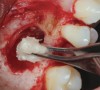

Fig 12. Lateral window sinus augmentation filled with a combination bone graft and PRF, to be covered by PRF membranes.

Figure 12